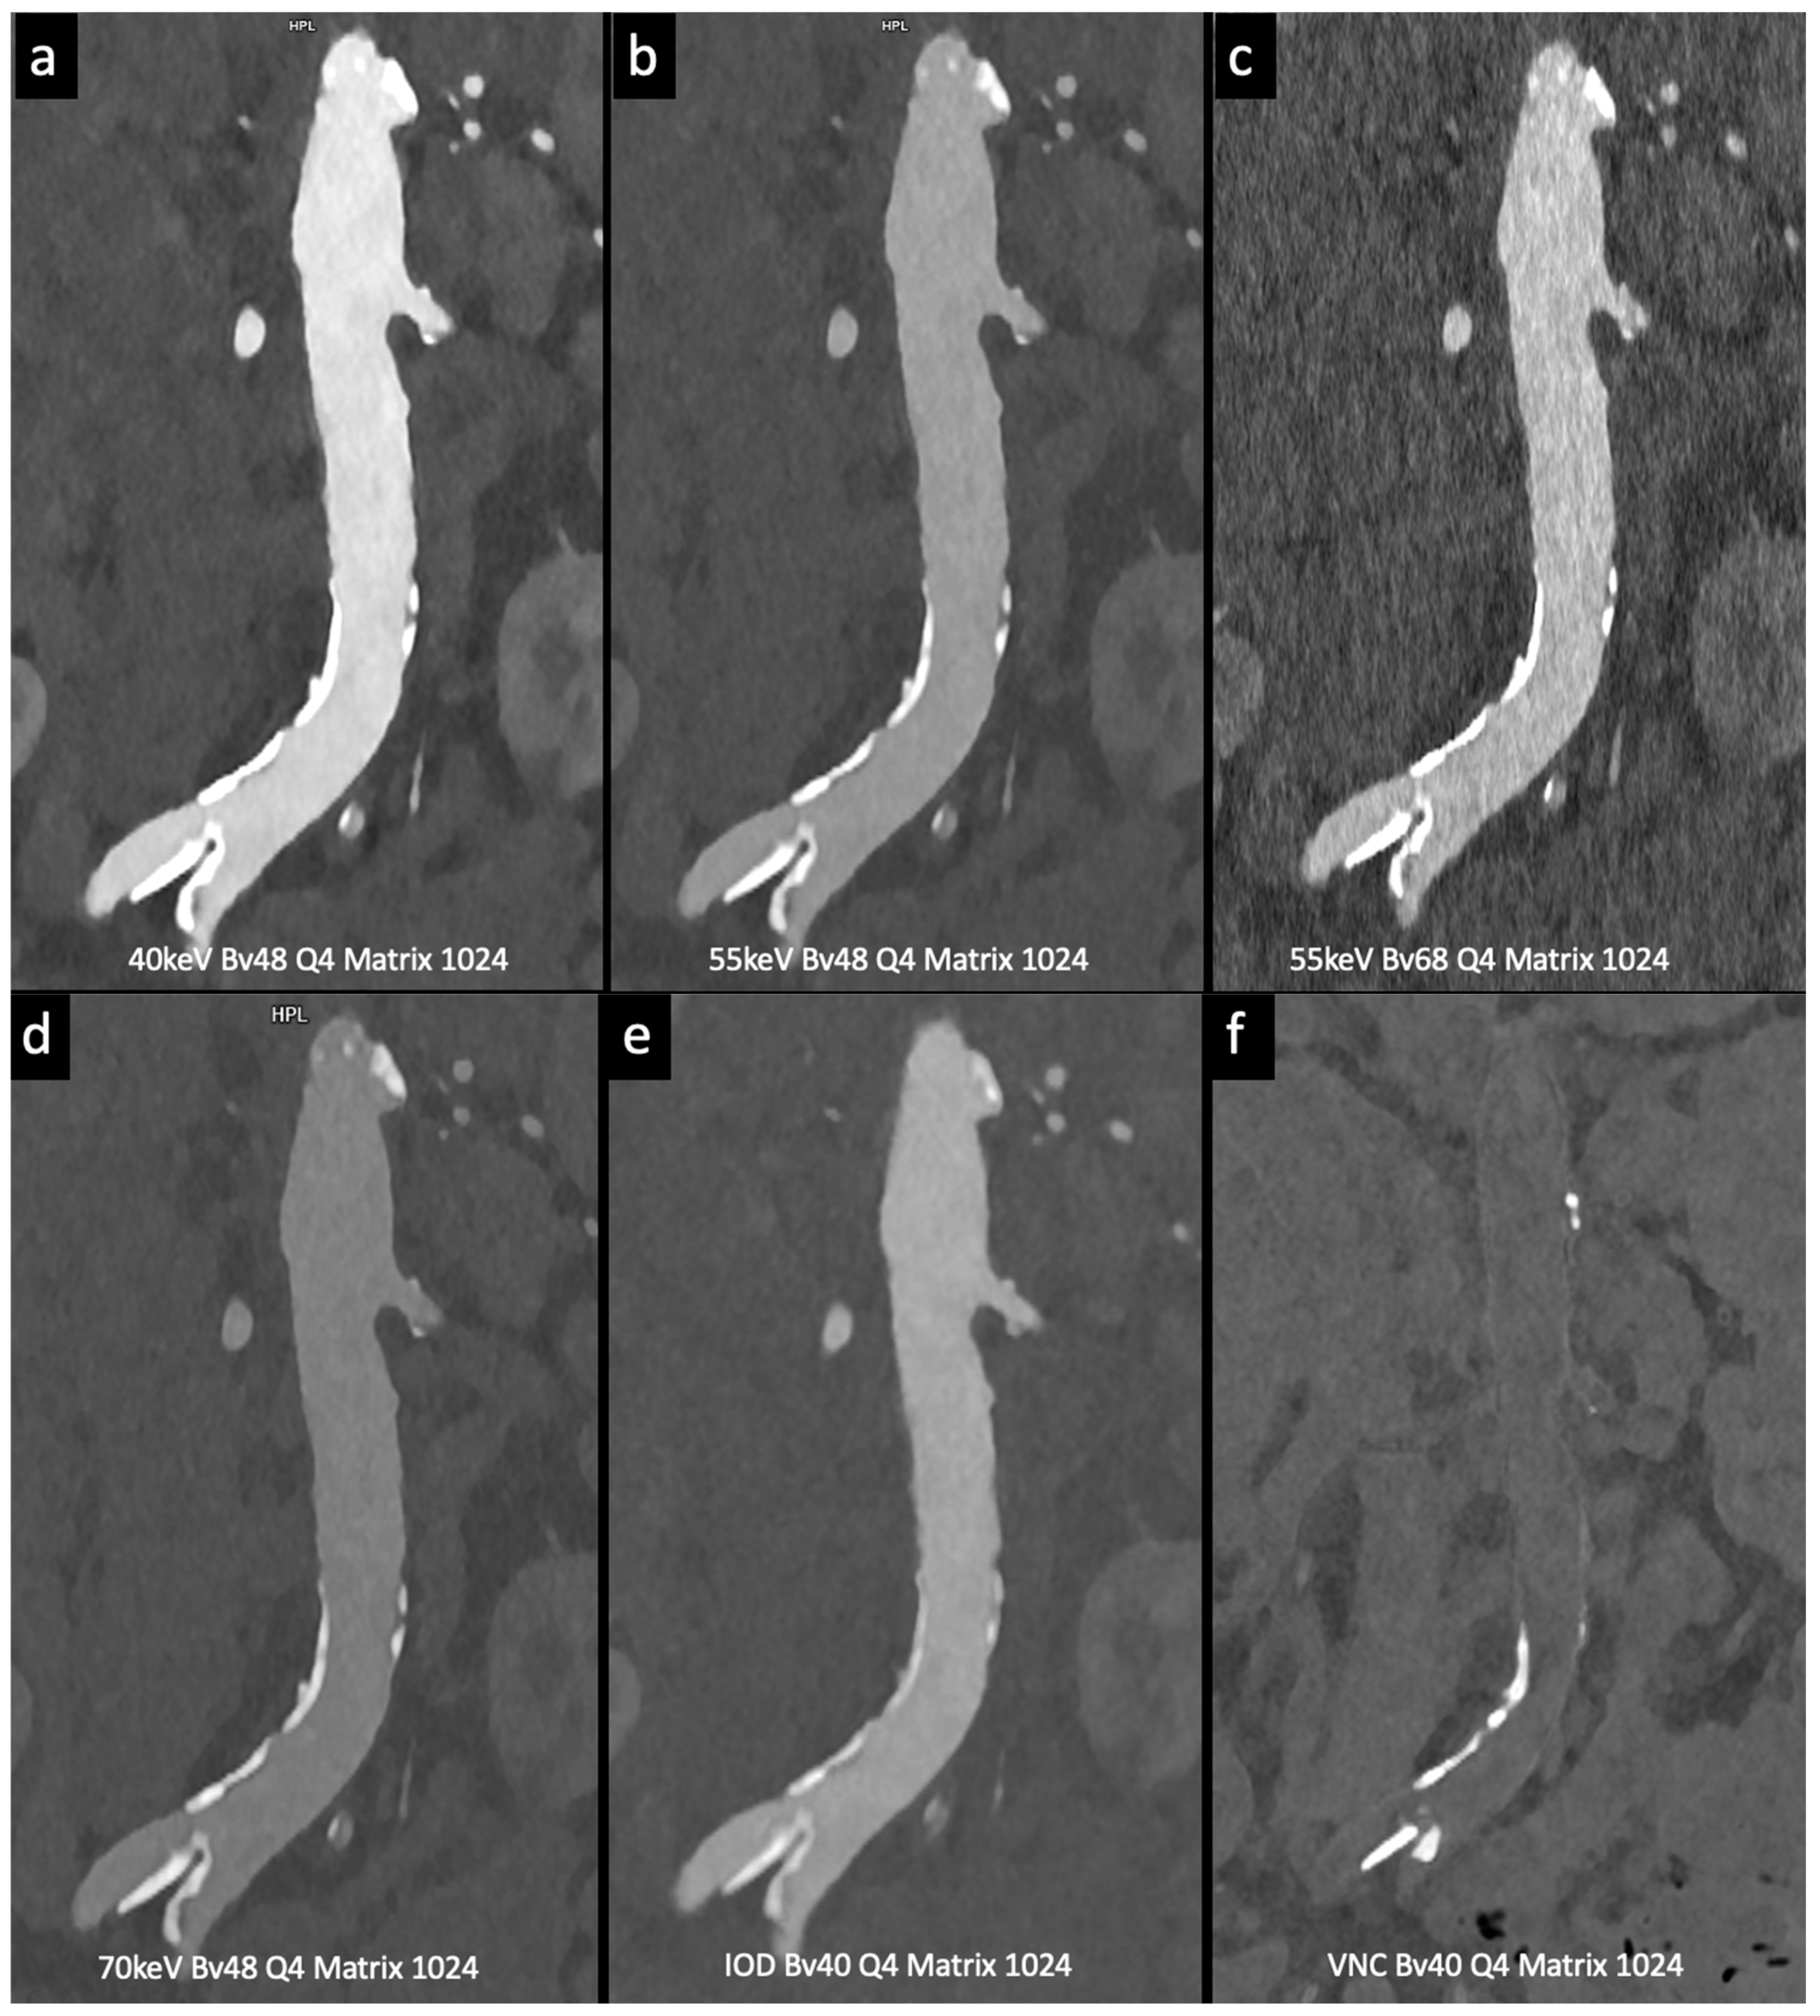

Higashigaito et al. [13] explored a low-volume contrast medium protocol for thoracoabdominal CT angiography using PCCT. This study compared PCCT with previous energy-integrating detector (EID) CT at equal radiation doses. Virtual monoenergetic images (VMI) at 50 keV exhibited the best trade-off between objective and subjective image quality, with a 25% higher CNR than that of EID CT. The low-volume contrast media protocol also reduced the volume of the contrast medium by 25%. These findings suggest that PCCT with a low-volume contrast media protocol achieves superior CNR while maintaining non-inferior image quality compared to EID CT (Figure 4).

Figure 4.

Comparison of image quality with photon-counting CT and standard contrast media. Abdominal aortic lumen with wall calcification coronal images. High Resolution images (Matrix 1024 × 1024) with different reconstruction kernels (window level W2000, C700): 40 keV Kernel Bv48, Q4 (a); 55 keV Kernel Bv48, Q4 (b); 55 keV Kernel Bv68, Q4 (c); 70 keV Kernel Bv48, Q4 (d); Iodine map reconstruction, kernel Bv40, Q4 (e); Virtual Non Contrast VCN reconstruction (f). Department of Radiology, Fondazione Toscana Gabriele Monasterio, Pisa, Italy.